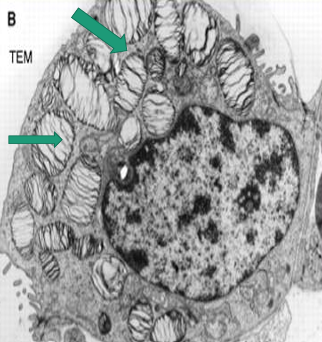

Type II pneumocyte

A -Identify the cell

B -Identify the labelled structure

A- pneumocyte type II

B- Lamellar bodies